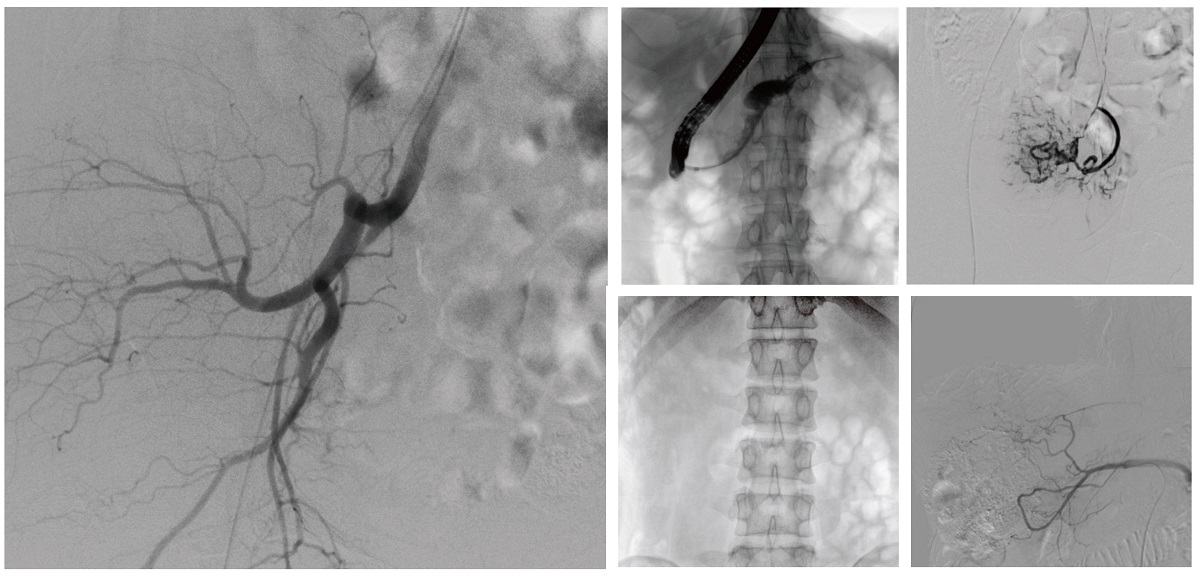

醫(yī)院引進(jìn)的普愛醫(yī)療移動(dòng)式平板介入中C,其高清成像能力覆蓋骨科、介入科、泌尿外科、婦產(chǎn)科等多科室,能夠滿足介入微創(chuàng)手術(shù)的多樣化需求。

設(shè)備的移動(dòng)式設(shè)計(jì),無需對(duì)現(xiàn)有手術(shù)室進(jìn)行改造,適合高負(fù)荷手術(shù)量或應(yīng)急情況下的靈活部署。如在急診介入手術(shù)中,該設(shè)備能迅速響應(yīng)需求,為醫(yī)生提供實(shí)時(shí)影像支持,提升搶救效率。